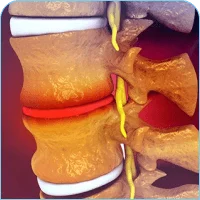

The spine is a complex of vertebrae, discs, joints, and ligaments that are connected with numerous nerves and muscle tendons. It gives stability, mobility, and safety to the spinal cord. Injury, degeneration, stress, and misalignment of any of these parts result in a situation where someone experiences constant pain and has limited movements.

Back Pain Diagnosis